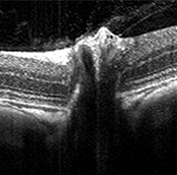

- OCT

Histology Images